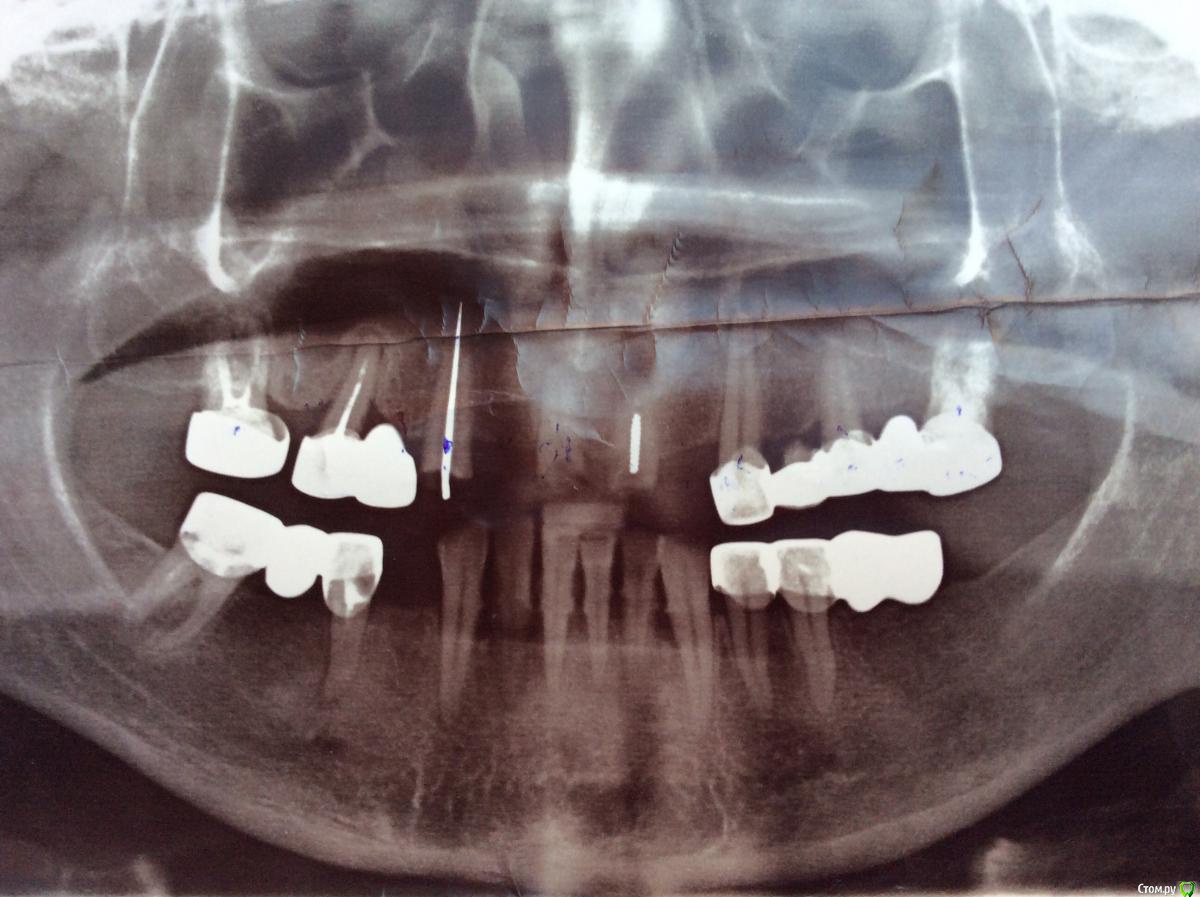

dr.Dre Опубликовано 18 сентября, 2015 Поделиться Опубликовано 18 сентября, 2015 Добрый день коллеги,пациентка 50 лет,вот такая картина 3,5,7,1 степени подвижности,хочет делать только вверх. Ссылка на комментарий

krokomot Опубликовано 18 сентября, 2015 Поделиться Опубликовано 18 сентября, 2015 Сначало разберитесь что на выход, потом что на эндо, то что останется будете протезировать. Мало зубов - иплантация или съемное. Ссылка на комментарий

molchanoff Опубликовано 18 сентября, 2015 Поделиться Опубликовано 18 сентября, 2015 уя консоль в 3 квадранте Ссылка на комментарий

NazranDantist Опубликовано 18 сентября, 2015 Поделиться Опубликовано 18 сентября, 2015 Добрый день коллеги,пациентка 50 лет,вот такая картина 3,5,7,1 степени подвижности,хочет делать только вверх.Все на выход и имплантация. 95%Или волшебный частичный съемник, мотивирующий на имплантацию)) Ссылка на комментарий

NazranDantist Опубликовано 19 сентября, 2015 Поделиться Опубликовано 19 сентября, 2015 Это уж слишком Конечно нужно больше информации для составления плана, но судя по снимку, только во 2-ом в сегменте что-то остается, но если говорить об имплантации, то я бы все убирал. А хорошие телескопы по цене будут примерно как все на 4-х имплантах. Ссылка на комментарий